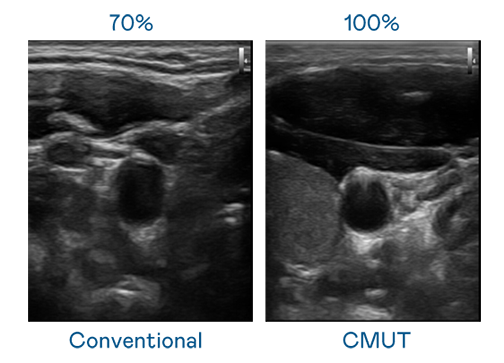

CMUT 技术是一种用电容式微机电元件来产生超音波讯号的技术。与传统 PZT 压电式技术相比,CMUT 频宽增加 30%,更宽频的超音波讯号让影像解析度大幅提升,是实现高影像品质医疗超音波扫描、促进精准医疗发展的关键技术。

大频宽带来超清晰影像

超音波影像的解析度高低,首先取决于探头能发出的讯号频宽。红蓝 CMUT 可提供高清晰的超音波讯号,提供高频宽、高灵敏度、影像纹理细节更高的超音波影像,协助医护人员缩短影像判读时间及利用精准的医疗影像进行诊断。